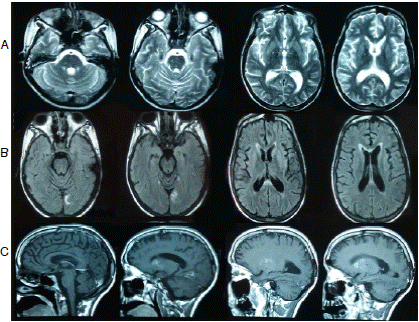

Pasado el primer mes tras el alta, la paciente fue evaluada medicamente para iniciar el proceso de rehabilitación neurológica y se reportó que permanecía postrada en cama, su interacción con el medio era limitada, seguía sin movimiento voluntario en las extremidades, abría los ojos de forma espontánea y no podía hablar. Se le hizo una resonancia magnética cerebral que sugirió la presencia de daño axonal difuso, pero el hallazgo no fue concluyente dado que fue necesario utilizar secuencias rápidas por las condiciones de la paciente (figura 1).

Figura 1 Resonancia magnética posterior a la hospitalización A. De izquierda a derecha: resolución de edema cerebral, infartos ‘lacunares’ en puente, núcleos de la base y tálamos. B. De izquierda a derecha: necrosis cortical laminar bilateral en corteza occipital (mayor compromiso izquierdo) y cambios en la señal del esplenio del cuerpo calloso (con gandolinio). C. De izquierda a derecha: infartos ‘lacunares’ en ganglios de la base y necrosis cortical laminar de predominio occipital izquierdo (con contraste)